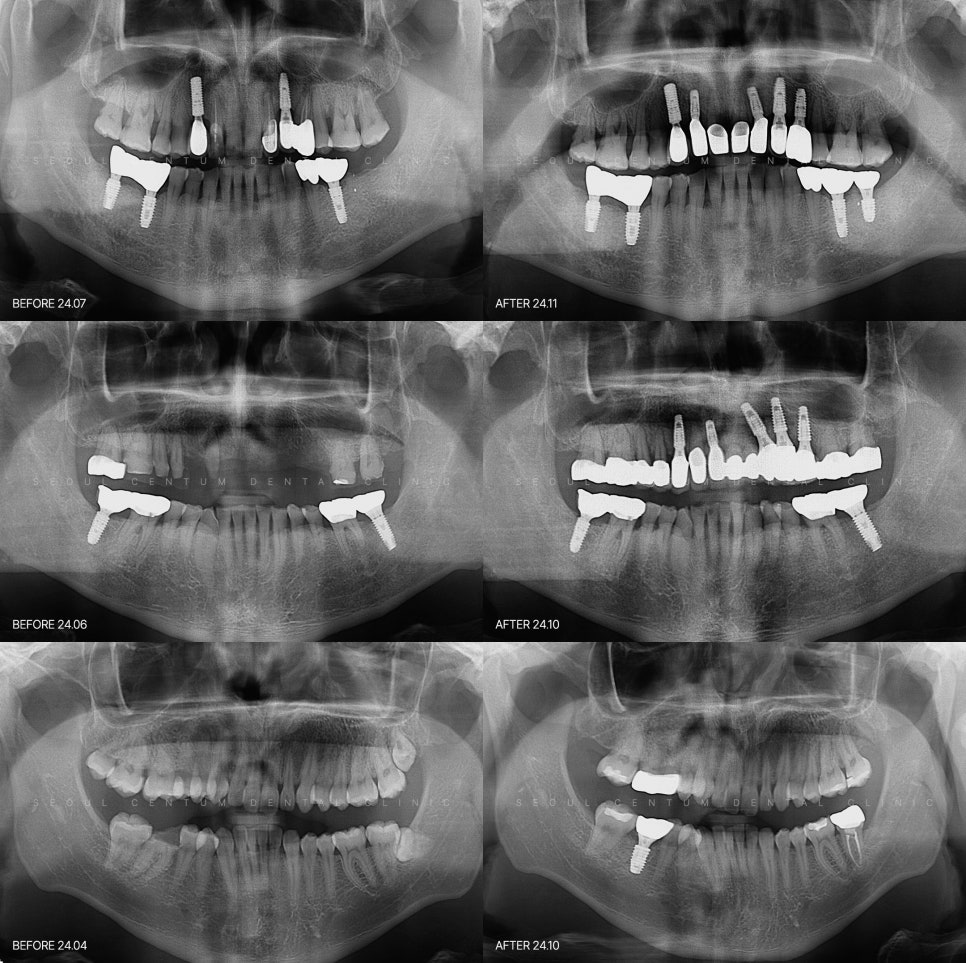

치과임플란트 근심 걱정 no 고려사항 4가지

40대 임플란트 치료케이스 상악동거상술 + 골이식